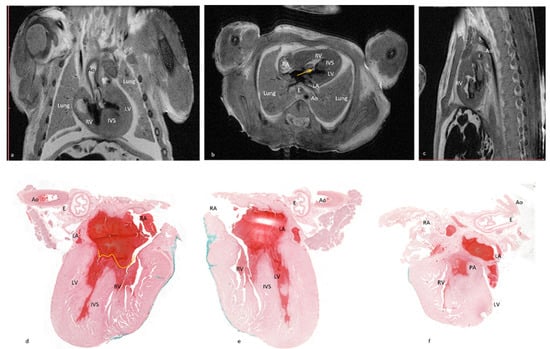

In case No.11, both methods diagnosed the complete atrioventricular canal but pm-MRI also diagnosed a hypoplastic left ventricle as well as an overriding aorta and arterial duct agenesis. Comparative images with observed lesions are depicted in Figure 5. Additionally, in case No.12, though both methods described most of the lesions, 4CCD failed to describe bilateral ventricular hypertrophy and a ventricular septal defect. Thus, 4CCD overdiagnosed an aortic valve stenosis and tricuspid valve stenosis. Comparative images are presented in Figure 6. Therefore, as shown in Table 2, the lowest sensitivity rate was observed in examining the arterial duct and left atrium. The disagreement was in two out of three cases, presenting anomalies on pm-MRI (cases No. 7 and 11). For the conventional dissection method, a minimum of six fine sections are required for evaluation of the atria, ventricles, and outflow tracts, whereas for the 4CCD method, only two parallel sections are required. External cardiac examination was described as a common step for both methods. Microscopic examination required more time for the 4CCD method, especially for malformed hearts, but it did not surpass the entire time needed for the stereomicroscopic cardiac examination. Our subjective assessment revealed that the 4CCD method required less time for examining fetal hearts than the conventional inflow–outflow method for very small fetal hearts.

Figure 5.

Presenting comparative images of the pm-MRI and microscopy of case No. 11. Note the small-sized left ventricle (a,b) and overriding aorta (a). (c) Sagittal section through mediastinum. Complete atrioventricular canal was observed on both examination methods. On the pm-MRI image (b), yellow arrow marks the ventricular septal defect and atrial septal defect. On the microscopic image (d), the yellow line highlights the atrioventricular valve passing over the ventricular septal defect. Interatrial septum is also absent. (d) The 4CCD heart section and hematoxylin-eosin stain, 0.4×. (e,f) The 4CCD heart section and hematoxylin-eosin stain, 0.5×.